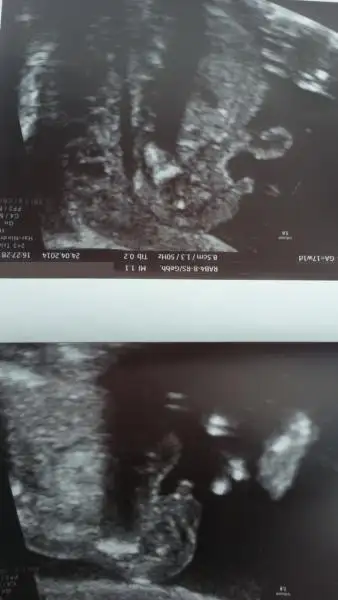

$20140424_191511.webp burdada 12 haftalik yuz ustu yatıyor. Doktor heniz penis cikintisi gozukmuyor belki kucuk oldugundandir.su an belli degil ama bana kiz gibi geldi dedi, sizin tecrubelerinize ddayanarak sizce prensesimmi gelicek prensimmi cvp yazarsaniz cok mutpu olurum bidahaki muaneme daha bi ay var beklemek baya zor:))

evet canim popo bölgesi direk orayi fotograf cektim zaten erkek diyorsun yani cokmu belli oluyor erkek oldugu 17.haftalik burda tesekkür ederim hayirlisi olsun insallah allah sagsaglim herkesin kalbine göre versin :emir_bebek::nazar:

cnm doktor soylemedimi cinsiyetini bu teoriyegore erkek ama allah gonlune gore versin